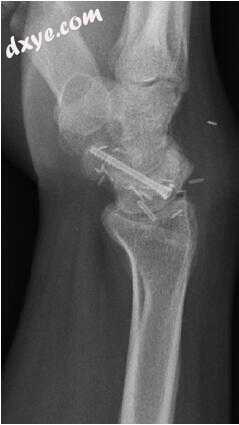

16.jpg

图.16  A,术前计算机断层扫描显示背侧闰节不稳定(DISI)。 术后前后位(B)和侧位视图(C),将DISI和Kirschner导丝从桡骨到月骨的复位。 (Courtesy of Scott W. Wolfe, MD.)